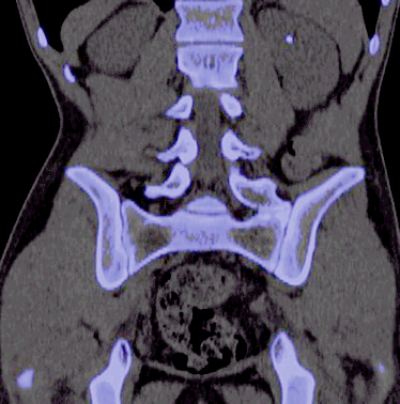

Figure 2: Graph used to ascertain stone composition using a dual-energy CT scanner.

The attenuation value of each calculus is plotted on a graph using software available on the CT scanner, with 140kV value on the x-axis and 80kV on the y-axis. Figure 2 demonstrates the graph and how different calculi appear. The software algorithm then produces a further image, where a uric acid calculus is shown as red and non-uric acid as blue.